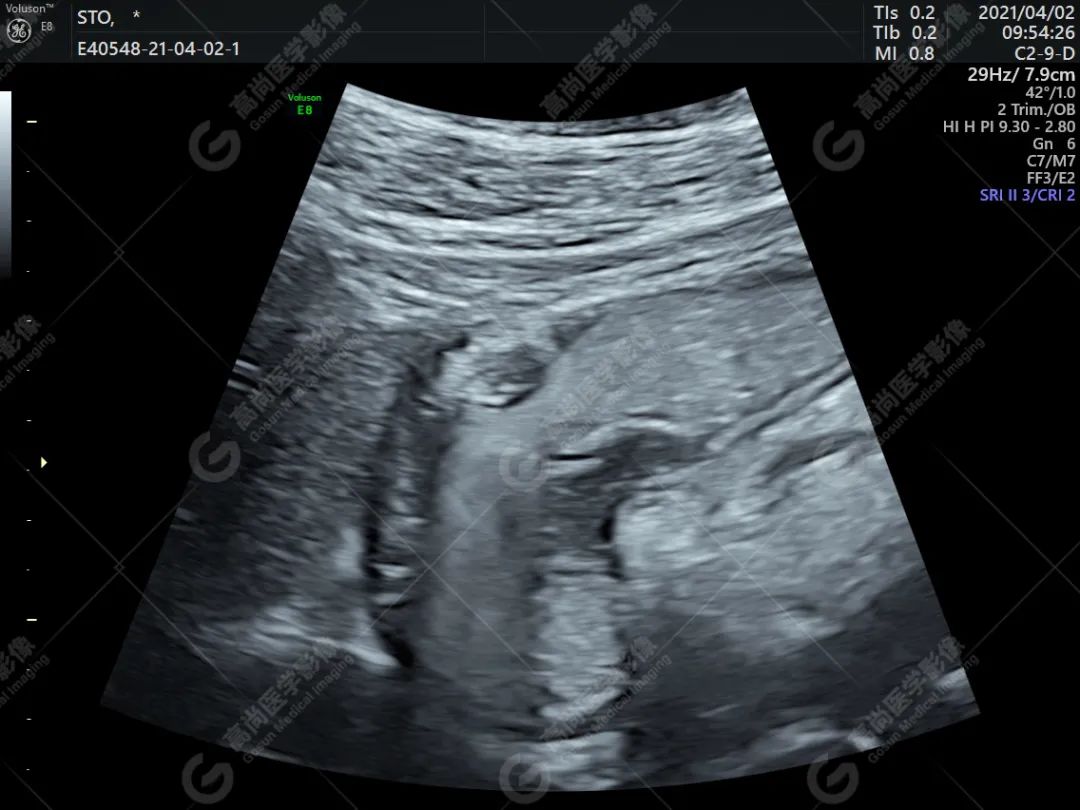

胃窦部大弯侧探及一实性低回声,大小约 9 mm×8 mm,起自粘膜层向胃腔内隆起,表面尚光滑,随胃蠕动而移动但不消失。

超声提示:胃窦部粘膜小肿块(考虑胃息肉;异位胰腺待排;建议进一步检查)。

2. 多起源于粘膜下层,其次为肌层,也可见于粘膜层和浆膜层。呈片状中等回声,局部放大可见网格状改变,类似胰腺回声。

3. 可伴有无回声的类导管样结构。

4. 异位胰腺向胃腔有个小的开口,呈脐样凹陷。脐样凹陷可作为异位胰腺的一种重要提示。

超声显示起自胃壁粘膜下层局限性均匀低回声肿物,直径在 2.0 cm 以内,其内部结构回声和胰腺组织类似,应怀疑本病。